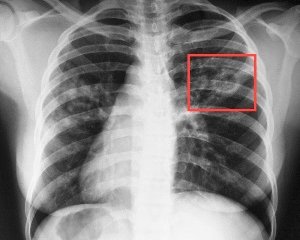

Начальные симптомы болезни включают в себя усталость и кашель, которые сохраняются более трех недель. Со временем в мокроте может появиться кровь, а также возникает дискомфорт при дыхании, поскольку легочные ткани начинают повреждаться. Появление этих признаков требует немедленного визита к врачу.

Начальная стадия туберкулеза у 10-15% больных не проявляется. Обнаружить ее можно только на снимке флюорографии. У 1/3 заболевших наблюдаются симптомы функционального характера, каковыми являются быстрая утомляемость, слабость, снижение работоспособности, повышенная раздражительность.